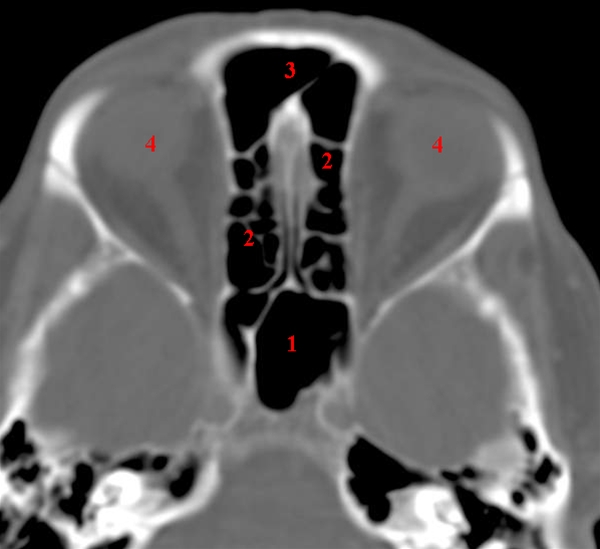

CT-snit i axialplan gennem sinus sphenoidalis og ethmoidalceller.

Basale del af sinus frontalis ses også.

1. Sinus sphenoidalis (kilebenshule)

2. Sinus ethmoidales (sibbenshule)

3. Sinus frontalis (pandehule)

4. Orbita (øjenhule)